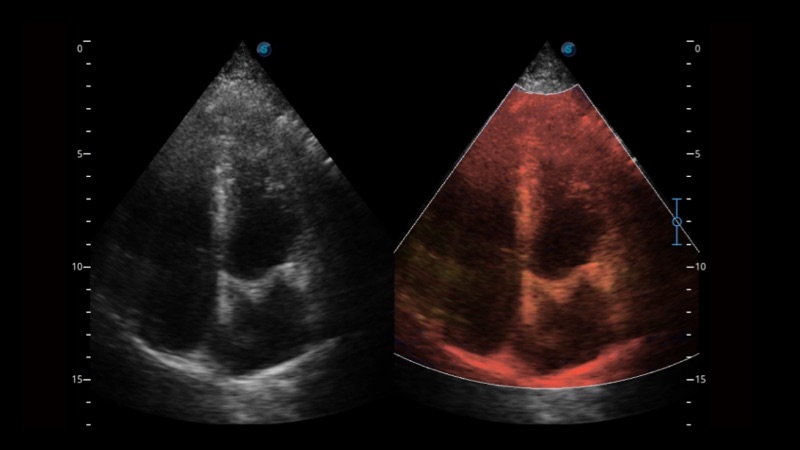

SR Flow高分辨率血流成像

高分辨率血流成像技术提高了对低速血流信号的检测能力。在提高空间分辨率的同时,也克服了血流外溢现象,为用户提供更加真实的血流动力学信息。

组织多普勒

组织多普勒成像功能,可提供心肌运动速度和其他临床信息,使临床医生能够分析和比较患者心脏不同部位的运动。

临床图像